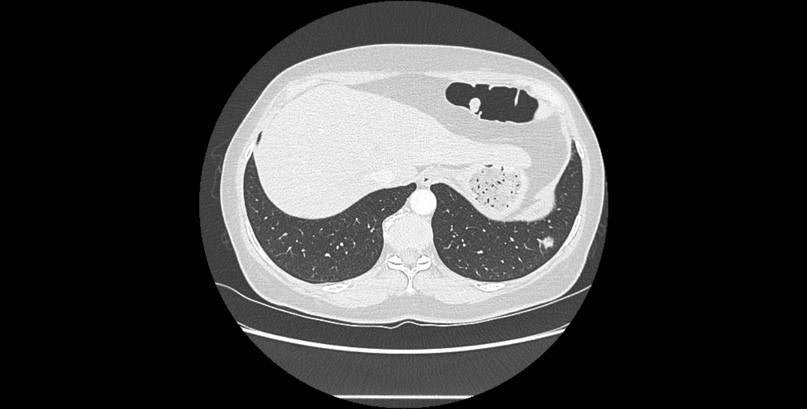

Une femme de 53 ans, ancienne fumeuse (20 paquets-années), sans antécédents médicaux chirurgicaux particuliers est adressée pour une prise en charge chirurgicale diagnostique et thérapeutique d’une lésion pulmonaire lobaire inférieure gauche suspecte. C’est lors d’un scanner abdominal qu’il a été mis en évidence un nodule basal gauche en mars 2024 de 12 mm résistant à une double ligne d’antibiothérapie (Figure 2). Le PET scanner ne retrouve pas d’hypermétabolisme franc suspect en regard de cette image latéro-basale gauche. L’IRM cérébrale ne retrouve pas de lésion suspecte. La fibroscopie bronchique est sans particularité.